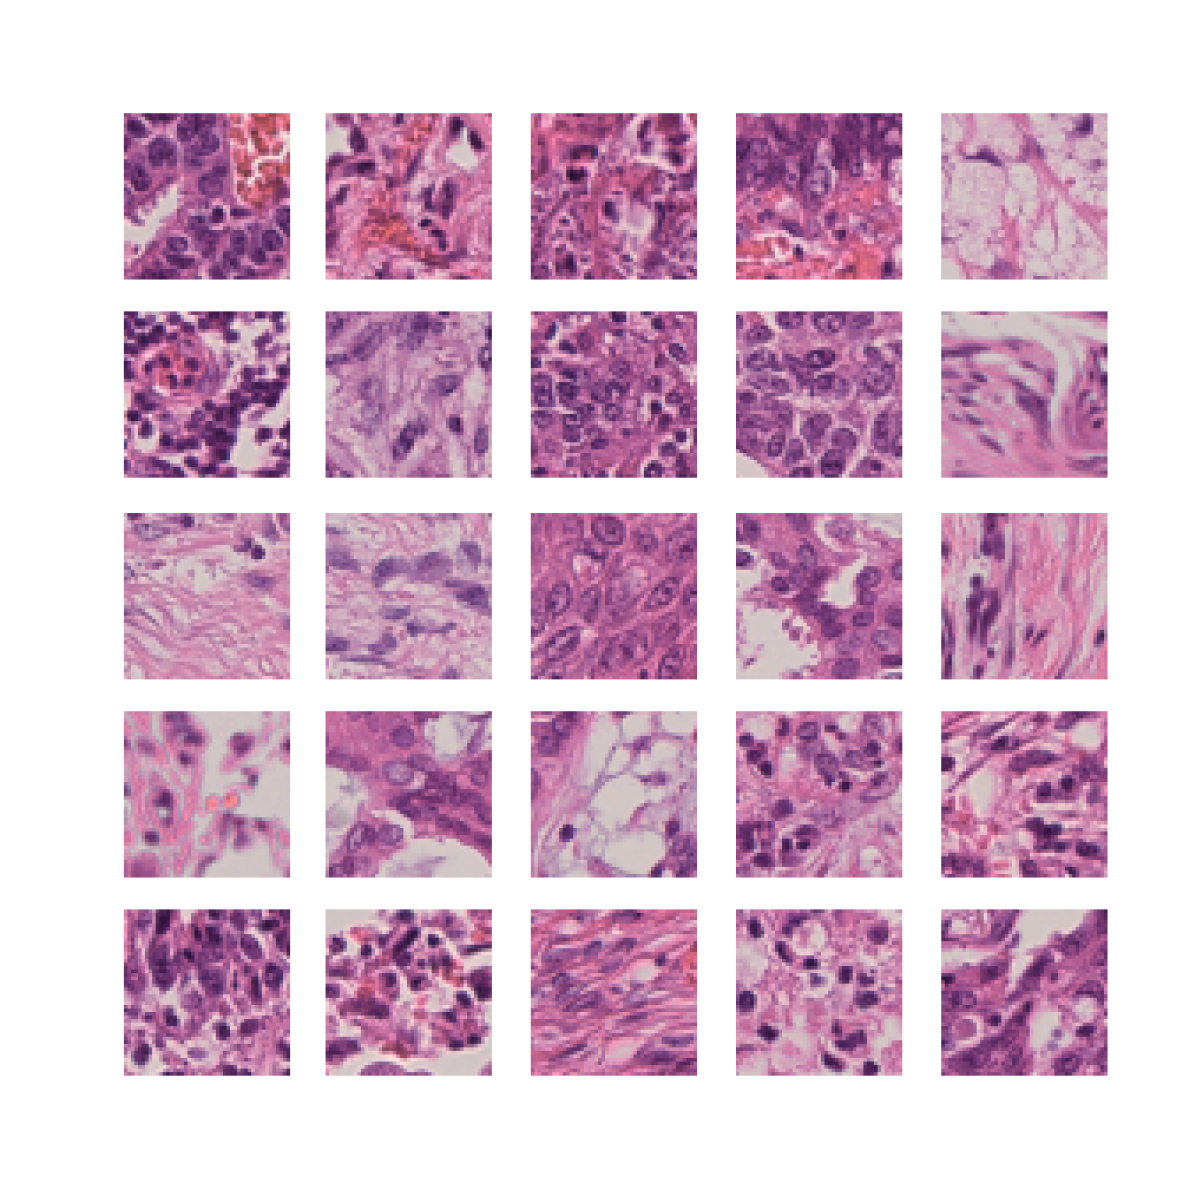

We also analyse the activation maps for each model using GradCAM as described in section S3. This offers more insight into the areas of the image which are contributing most heavily to the models’ representations. In Figure 4(b) we present some representative examples, however, a larger selection which was chosen at random is presented in Figures S10 to S25. The larger selection makes it easier to see the emergent patterns, including that privileged Siamese models tend to mainly identify features which are strongly present in both inputs, while unprivileged Siamese models tend to learn more diffuse features that are not specific to one cell phenotype or image region. TriDeNT ♆ incorporates both sets of features, learning both features specific to the privileged data and more the general features associated with unprivileged Siamese networks.

We can see in Figure 4(b) panel A that for ERG, the privileged Siamese model focuses almost exclusively on any nuclei which could be endothelial cells. As there are very few endothelial cells in the dataset, it could be an effective strategy to identify anything that could potentially be an endothelial cell to minimise the difference between the representations of the H&E model and the IF mask model. In the corresponding unprivileged Siamese image, we see that the model identifies some of these nuclei, albeit less strongly, but also focuses heavily on the other tissue and even the background, while strongly fixating on two spots of debris in the center of the image. This model has less ‘incentive’ to learn the weak features related to endothelial cells as these occur rarely and are not easy to detect, while more generic strong features such as the presence of connective tissue and the prevalence of background are more common and predictable from augmented images. We see that TriDeNT ♆ combines these two feature sets, strongly identifying nuclei while also identifying the connective tissue.

In panel C we see a similar pattern, with the privileged Siamese model fixating solely on the nuclei, while the TriDeNT ♆ model takes a more balanced approach. The unprivileged Siamese model appears to focus on a single cluster of nuclei while neglecting others, and similarly identifies an area of fibroblasts with its distinctive pattern but does not others.

In contrast to panels A and C which represent models with poor privileged Siamese results, panels B and D represent models whose privileged Siamese results were comparable to both TriDeNT ♆ and even the supervised baseline. It is therefore interesting to note that there are far more similarities between the privileged Siamese and TriDeNT ♆ models in both cases. Particularly in panel B, TriDeNT ♆ and the privileged Siamese model return virtually identical heatmaps, with both strongly identifying epithelial nuclei and neglecting the same areas of connective tissue. The unprivileged model in this case appears to focus solely on the centre of the image, giving a significantly different heatmap to the other panels.

Panel D again shows the previous pattern, with the privileged Siamese model identifying the features strongly present in the privileged data – fibroblasts – while neglecting the nuclei present. TriDeNT ♆ also strongly identifies the connective tissue, but, unlike the privileged Siamese model, does not completely neglect the nuclei. The unprivileged Siamese model primarily identifies background, and does not appear to identify the nuclei in this example.